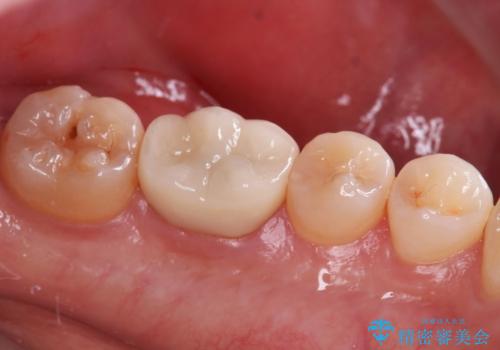

奥歯に虫歯があると言われた セラミッククラウンでキレイで長持ちする歯へ

担当医 榊原康平